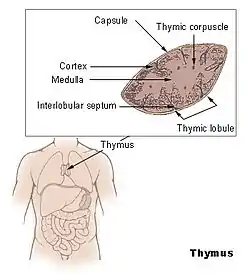

The thymus (pl.: thymuses or thymi) is a specialized primary lymphoid organ of the immune system. Within the thymus, thymus cell lymphocytes or T cells mature. T cells are critical to the adaptive immune system, where the body adapts to specific foreign invaders. The thymus is located in the upper front part of the chest, in the anterior superior mediastinum, behind the sternum, and in front of the heart. It is made up of two lobes, each consisting of a central medulla and an outer cortex, surrounded by a capsule.

The thymus is an organ that sits behind the sternum in the upper front part of the chest, stretching upwards towards the neck. In children, the thymus is pinkish-gray, soft, and lobulated on its surfaces.[1] At birth, it is about 4–6 cm long, 2.5–5 cm wide, and about 1 cm thick.[2] It increases in size until puberty, where it may have a size of about 40–50 g,[3][4] following which it decreases in size in a process known as involution.[4]

The thymus is located in the anterior mediastinum.[5] It is made up of two lobes that meet in the upper midline, and stretch from below the thyroid in the neck to as low as the cartilage of the fourth rib.[1] The lobes are covered by a capsule.[3] The thymus lies behind the sternum, rests on the pericardium, and is separated from the aortic arch and great vessels by a layer of fascia. The left brachiocephalic vein may even be embedded within the thymus.[1] In the neck, it lies on the front and sides of the trachea, behind the sternohyoid and sternothyroid muscles.[1]

Microanatomy

The thymus consists of two lobes, merged in the middle, surrounded by a capsule that extends with blood vessels into the interior.[2] The lobes consist of an outer cortex rich with cells and an inner less dense medulla.[4] The lobes are divided into smaller lobules 0.5-2 mm diameter, between which extrude radiating insertions from the capsule along septa.[1]